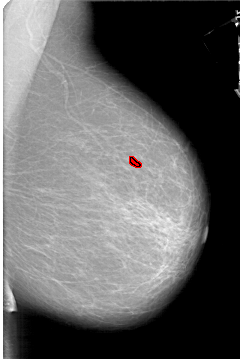

A_1333_1.RIGHT_CC

RIGHT_CC LINES 6736 PIXELS_PER_LINE 4336 BITS_PER_PIXEL 12 RESOLUTION 43.5 OVERLAY

FILE: A_1333_1.RIGHT_CC.OVERLAY

TOTAL_ABNORMALITIES 1

ABNORMALITY 1

LESION_TYPE CALCIFICATION TYPE PLEOMORPHIC DISTRIBUTION CLUSTERED

ASSESSMENT 4

SUBTLETY 2

PATHOLOGY BENIGN

TOTAL_OUTLINES 1

BOUNDARY